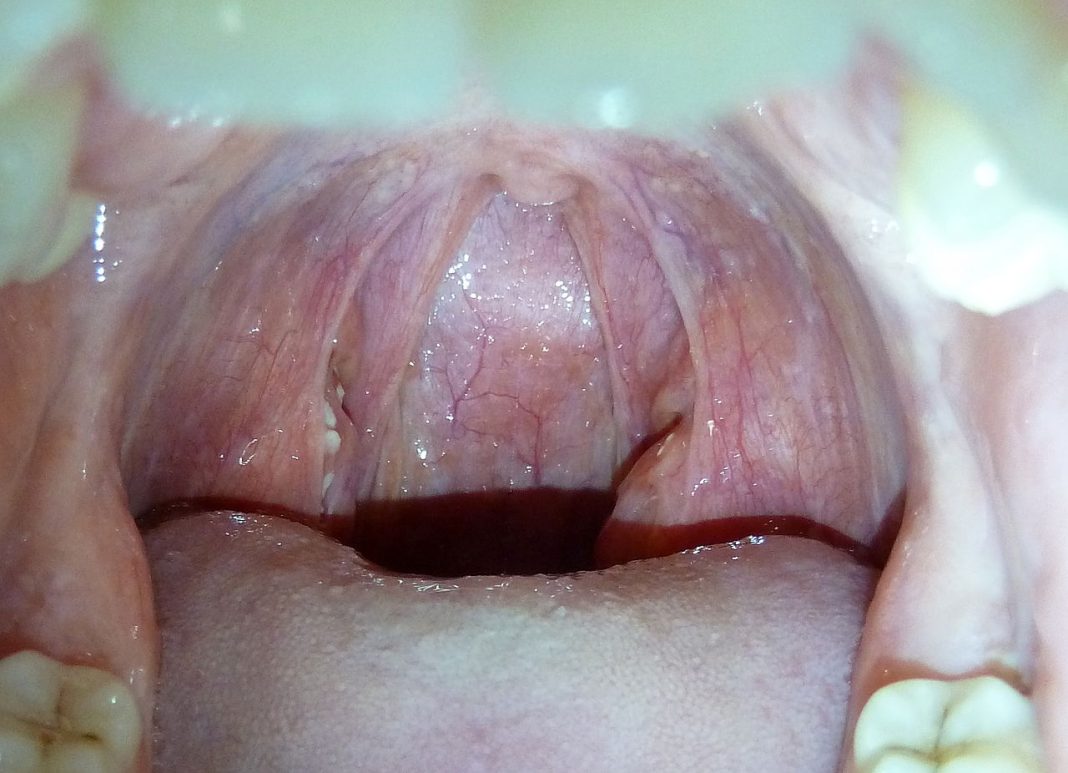

Exprimări de felul celor din titlul articolului – „Mă doare amigdalita/apendicita” – se pot auzi frecvent. Amigdalita (cu forma de plural amigdalite) este o boală manifestată prin inflamarea (acută sau cronică) a amigdalelor – din fr. „amygdalite” (DEX), iar amigdala (plural amigdale) denumește fiecare dintre cele două glande de natură limfatică, situate de o parte și de alta a omușorului – din fr. „amygdale”.